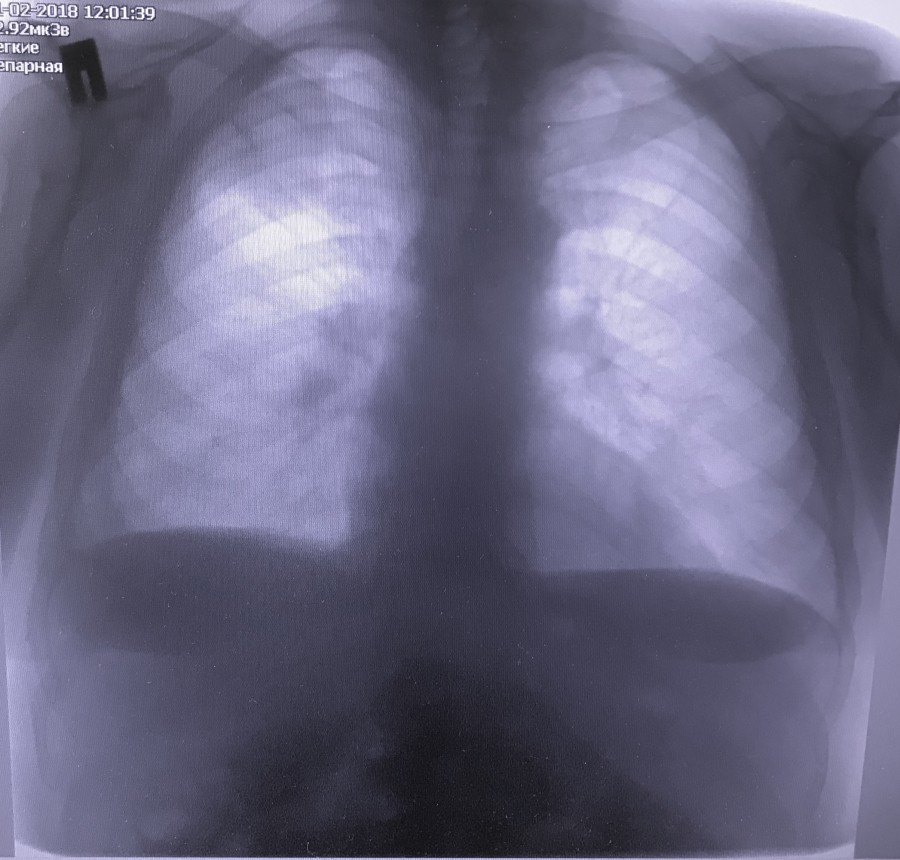

Заголовок сообщения: Периферическое образование

Обсуждалось здесь https://vk.com/club84409679?w=wall-84409679_7933%2Fall

1.jpg

1.jpg [ 135.84 KiB | Просмотров: 33041 ]